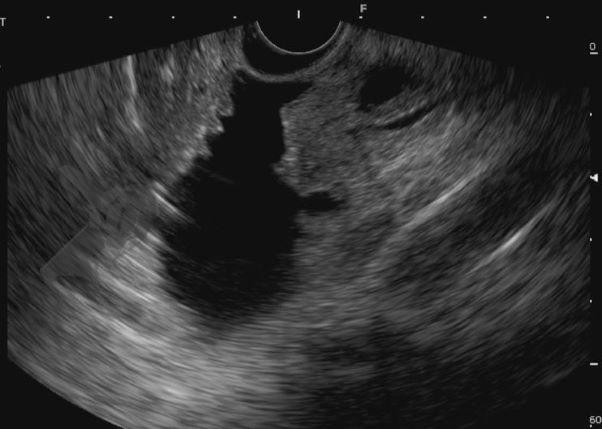

Diante da confirmação histológica de adenoma tubular com displasia de baixo grau, optado pelo estadiamento local através de ultrassom endoscópico (EUS), evidenciando lesão restrita a mucosa (sem sinais de acometimento de camada muscular) medindo 12×9 mm, com dilatação de colédoco até 9 mm e ausência de extensão intraductal.

O estadiamento deve seguir a classificação TNM e pode ser realizado por tomografia computadorizada (TC), colangioRNM, EUS e ultrassom intraductal. Nota-se a superioridade do EUS na avaliação do T (principalmente em lesões maiores do que 2 cm e T1) e da colangioRNM na avaliação do N. Ademais, a avaliação da extensão intraductal da lesão se faz necessária para definição do tratamento4.